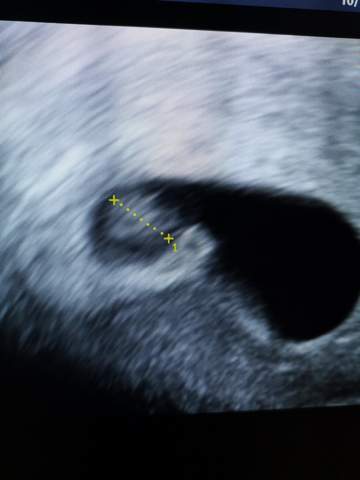

8 ssw ultraschall. Größe und Entwicklung des Embryos Der 2 Schwangerschaftsmonat geht zu Ende!. 8 SSW Ultraschall Deines Babys in der 8 Schwangerschaftswoche In der 8 SSW ist der Embryo 16 Millimeter groß Ab Ende dieser Woche ist sogar der Herzschlag beim Ultraschall zu erkennen und Herz und Kopf sind getrennt voneinander darstellbar In der jetzigen Entwicklungsphase tritt eine kleine Schleife des Darmes in einen Abschnitt der Nabelschnur über, weil die Bauchhöhle noch zu klein ist, um ihn ganz aufzunehmen. Das zeigt der Ultraschall in der 8 Schwangerschaftswoche Spätestens gegen Ende der 8 Schwangerschaftswoche ist der Herzschlag des Kindes auf dem Ultraschall zu erkennen Ein absolut unglaubliches und einzigartiges Gefühl, an dass ihr euch noch sehr lange erinnern werdet.

8 SSW Ultraschall Das ist zu sehen Am Ende des zweiten Monats der Schwangerschaft (8 Woche) ist aus dem mikroskopisch kleinen Zellklümpchen ein 9 bis 16 Millimeter großer Minimensch geworden Er hat jetzt winzige Hände und Füße, wobei sich die oberen Extremitäten etwas „schneller“ entwickeln als die unteren. Habe am Dienstag einen Termin beim Arzt, bin dann 72 Was wird auf dem Bild zu erkennen sein?.